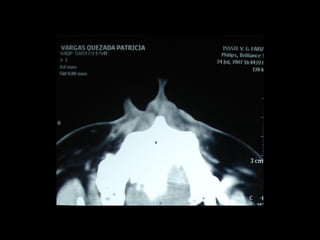

Quiste seno maxilar

Quiste mandibular